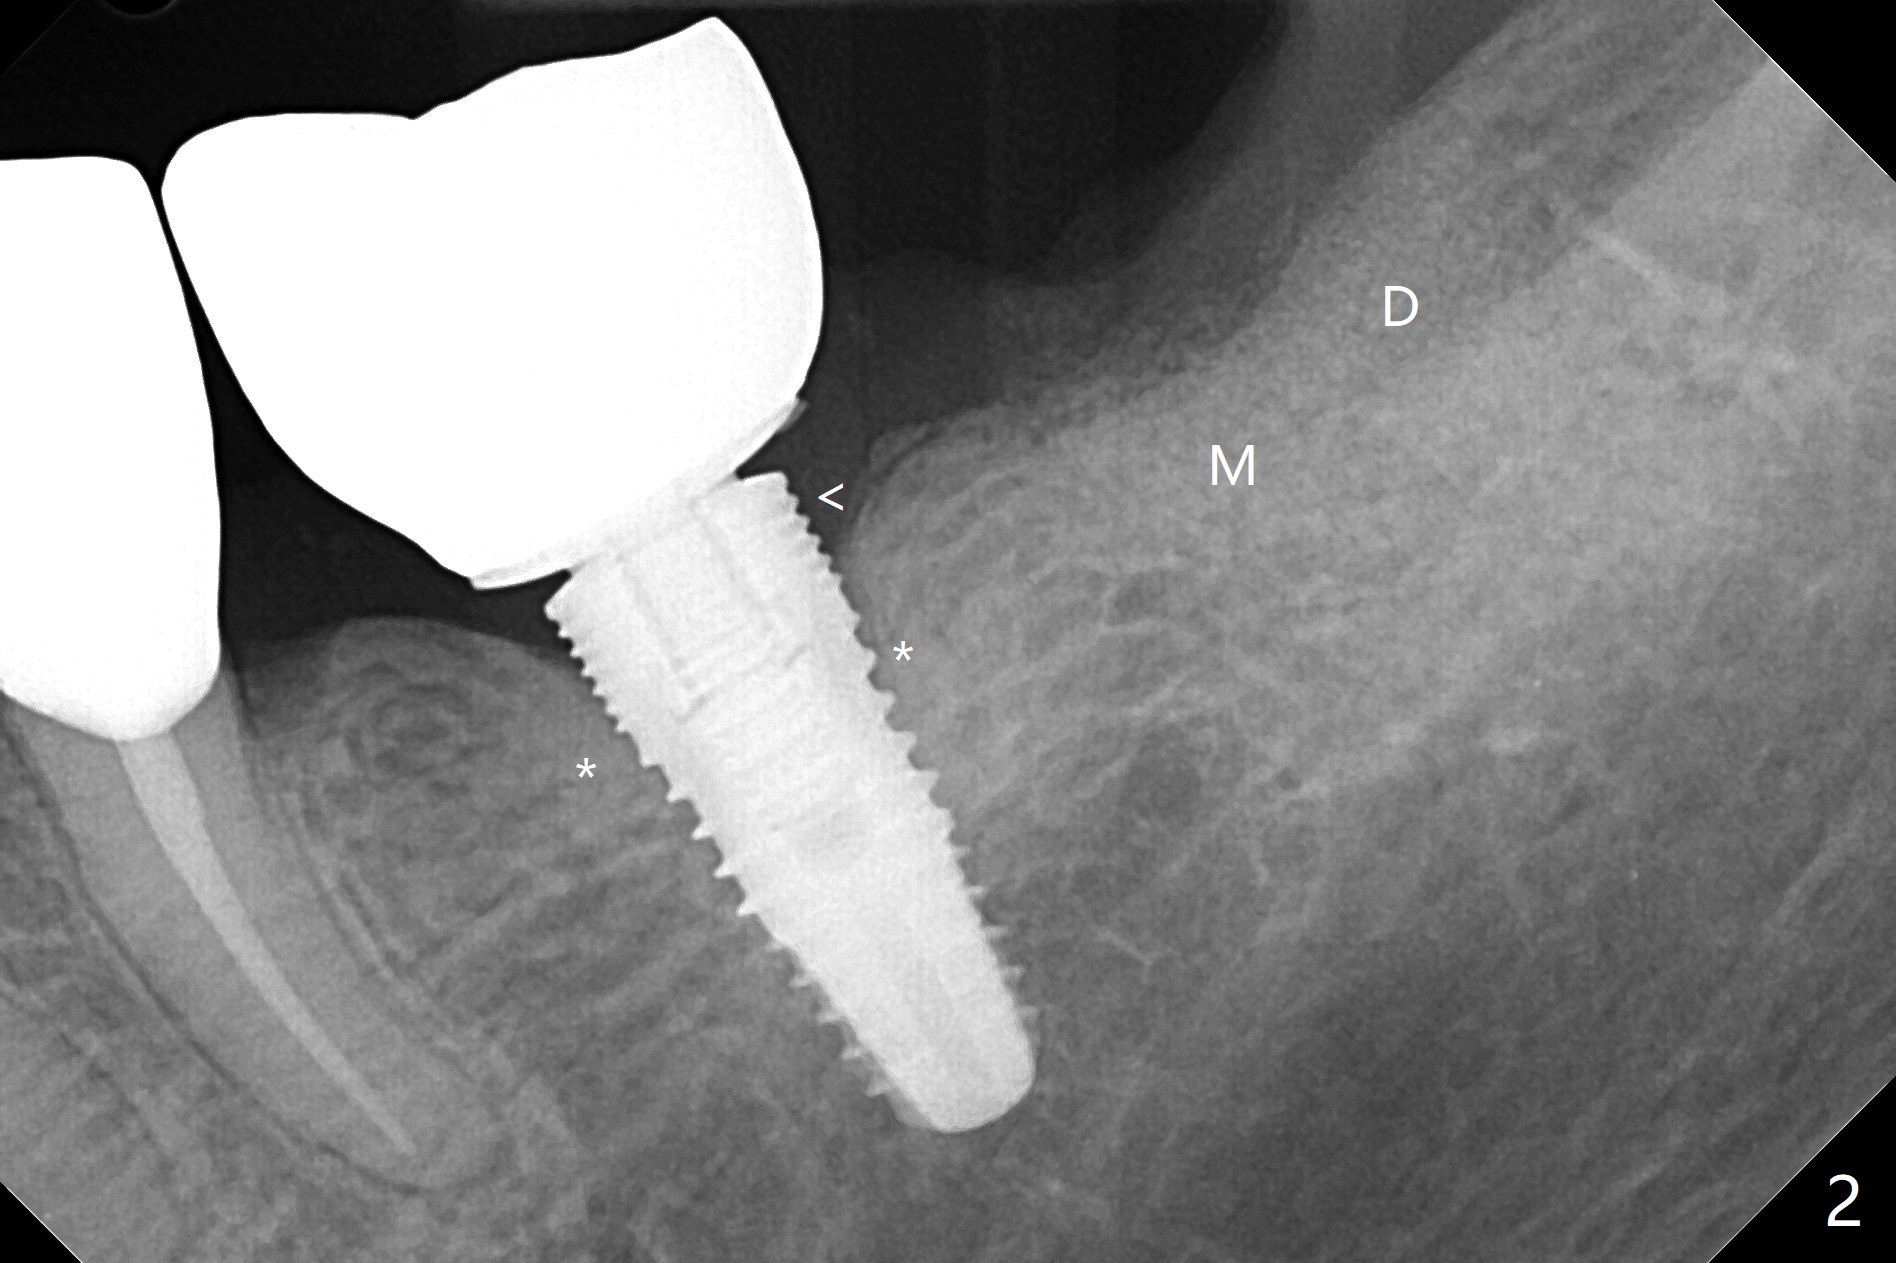

A 74-year-old woman is nervous with possible extraction and implant at #18 with subgingival caries (Fig.1 *), because 4 of immediate implants have been and possibly need to be redone. In contrast delayed implant at #19 fair the best with formation of the dense bone next to the coronal macrothreads (Fig.2 *) in spite of exposure of the microthreads (<). When the tooth #18 is extracted, the socket opening appears to be narrow. The lingual septum is narrow and short (possible C canal). Fine particles of cortical allograft mixed with blood is placed in the mesial (M) and distal (D) sockets and covered by compressed collagen plug and Cytoplast. PTFE suture is used. The future implant should be small in diameter and placed subcrestal. Acrylic dressing is in place and loose 2 weeks postop (Fig.3), presuming keeping Cytoplast in place. The dressing is going to be removed 5 weeks postop.